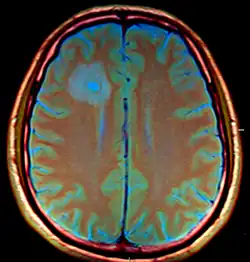

Amoebic brain abscess

| Amoebic brain abscess caused by Entamoeba histolytica | |

The CT images for the abscesses caused by Entamoeba histolytica are completely indistinguishable from the abscesses caused by any other organisms or causative agents. However, the brain abscesses are often observed in the frontal lobe or the basal ganglial regions.[1]